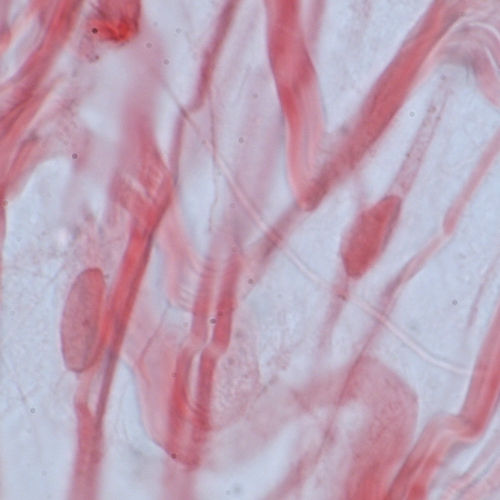

Differences among the connective tissues also depend on the three-dimensional organization of the molecular components. The type I collagen fibrils in tendon are packed into thick, parallel bundles of fibres, whereas type I collagen fibrils in skin are randomly oriented. In cortical bone, helical arrays of type I collagen fibrils are deposited around haversian canals.

Slide 17 Identify: Dense regular connective tissue Cross and longitudinal section of a tendon